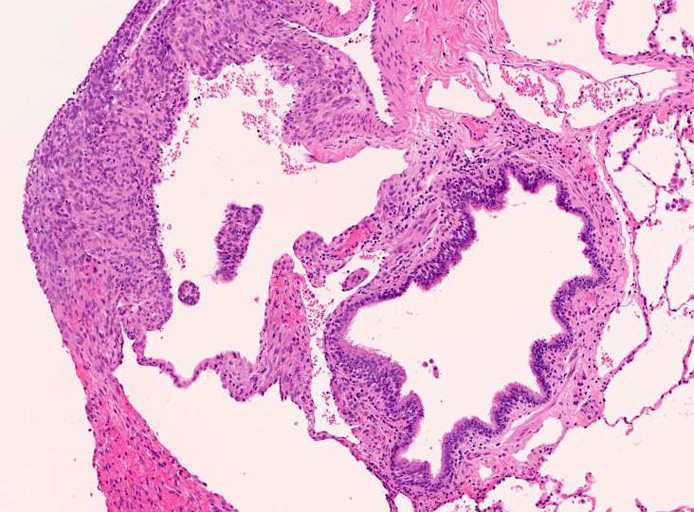

LAMの肺病変

嚢胞周囲または肺血管, リンパ管, 細気管支にそうLAM cellの浸潤, 集簇を特徴とする。LAM cellには2種類が認められ, 小型紡錘形細胞と細胞質の豊富な類上皮様細胞があり, 紡錘型は主に集簇巣の中心に存在し増殖能が高い。 類上皮様LAM cellは辺縁部に多く, 増殖能は低いがHMB45を強く発現している。

LAM cellの免疫染色--SMA, desmin, vimentin(vimentinはいつも陽性とはならない)が陽性となりmuscle lineageであるが典型的な筋細胞と異なり,

嚢胞形成はLAM cellの増殖と関連しており, 細胞が産生するmatrix metalloproteinases(MMPs)による組織破壊によるらしい。